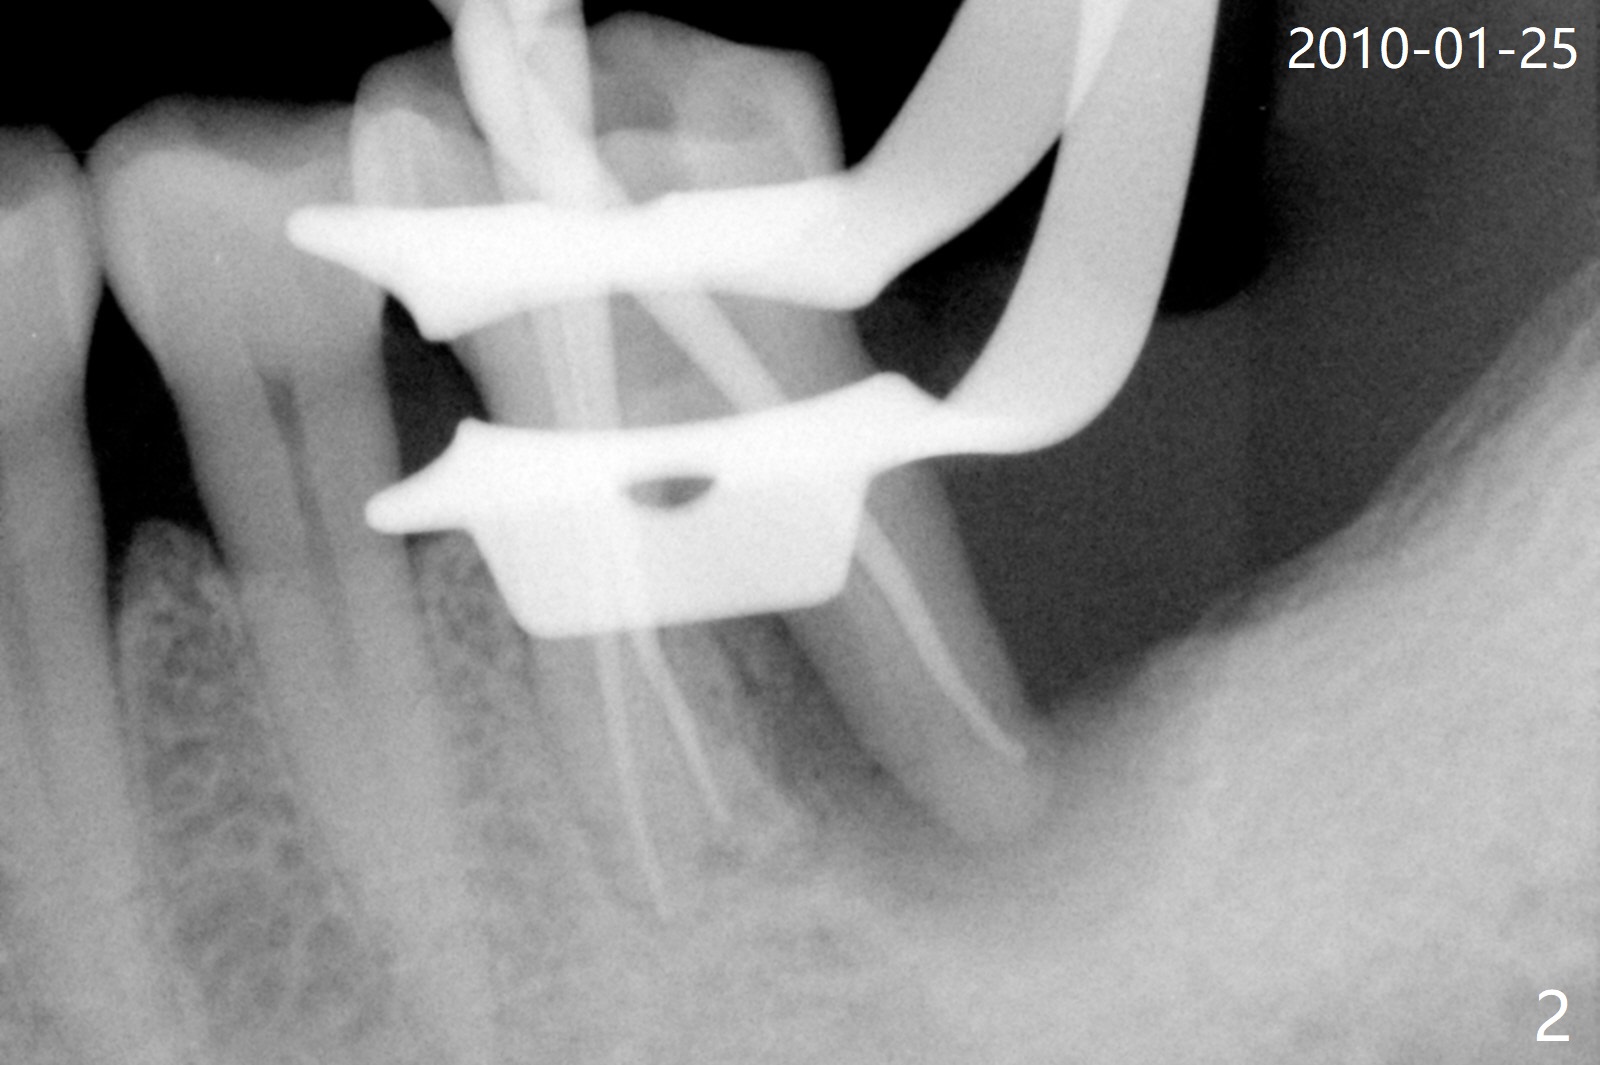

A 56-year-old man had distal gingival erythema at #19 with a fistula (Fig.1). Upon opening the pulpal chamber, the pulp is vital in the mesial canals, while necrotic distal. Root canal therapy is finished 1.5 months later (Fig.2). Although the patient was pleased with the treatment, the gingival infection and fistula did not improve. The tooth mobility increases over the years (Fig.3). He will return for evaluation next Monday. What should be done?